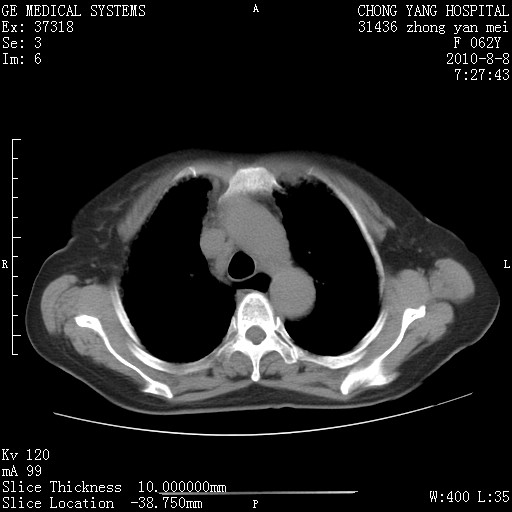

标题: CT28269:F62Y咳嗽胸痛数月。 [打印本页]

标题: CT28269:F62Y咳嗽胸痛数月。

两肺弥漫性间质纤维化伴继发性支扩。

考虑特发性肺间质纤维化

考虑两肺间质性肺炎并肺间质纤维化。

双肺间质纤维化合并感染、肺气肿

1.肺间质纤维化.

2.纵隔淋巴结肿大。

3.迷走右锁骨下动脉。

两肺间质改变,纵隔淋巴结肿大,需要考虑结节病的可能。